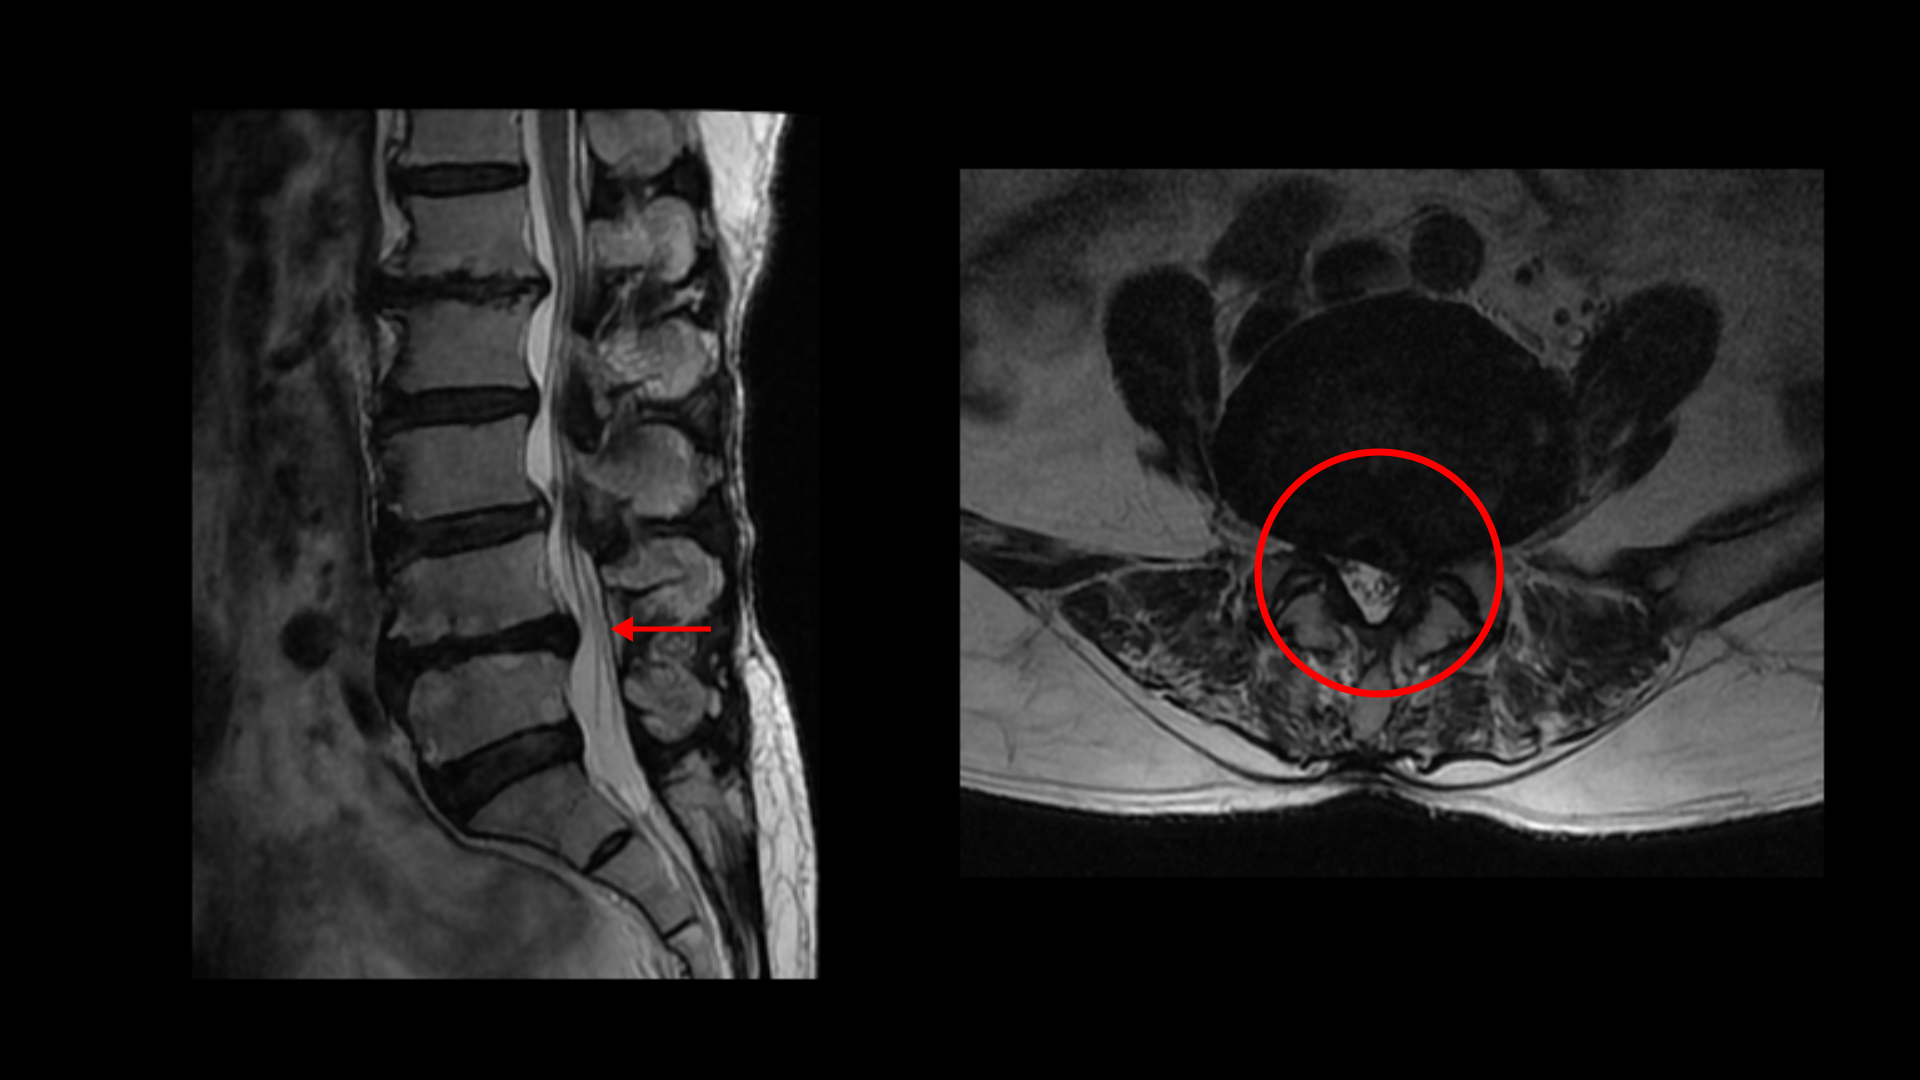

이분 MRI를 보면 허리 다섯 마디에 전부 퇴행성 디스크가 있습니다.

4-5번에는 왼쪽으로 디스크가 밀려 나와있고 심한 중심성 협착과 왼쪽 추간공협착도 있습니다.

5-1번에는 왼쪽으로 디스크가 밀려 나와있고 전반적으로 왼쪽이 상태가 더 안 좋은데 이분의 증상도 왼쪽 엉덩이와 다리의 통증과 저림 및 마비감입니다.